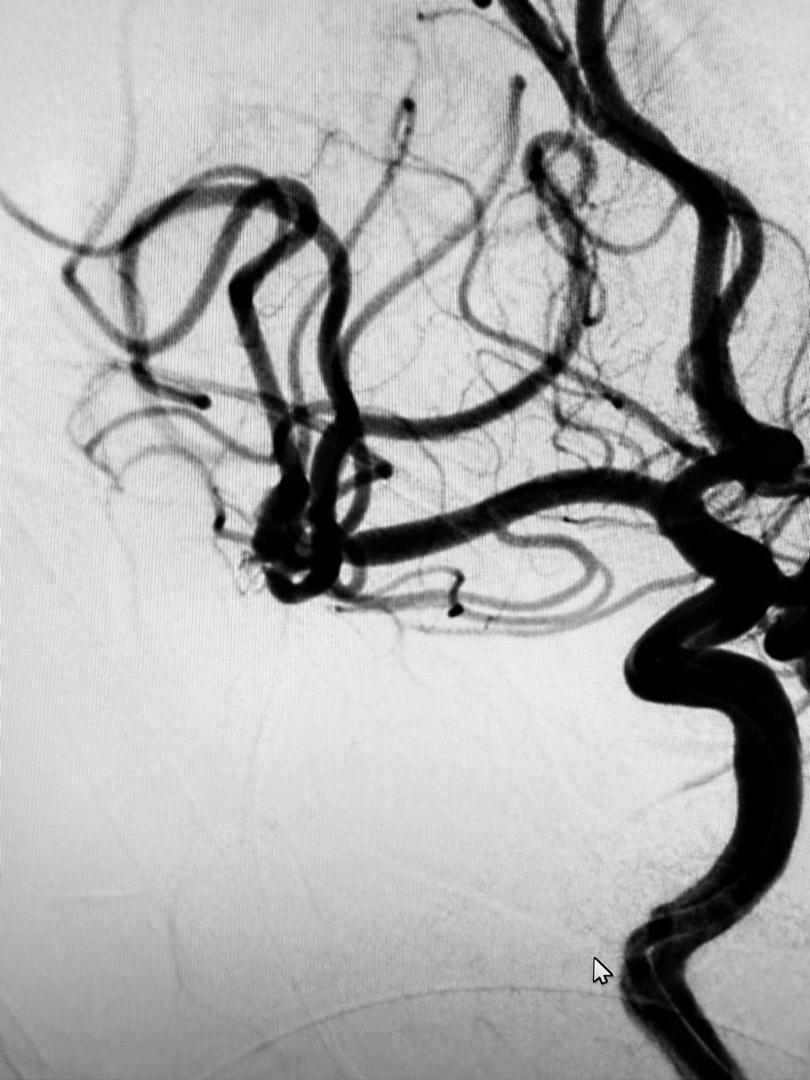

“The coil was electrically detached once securely positioned, filling the aneurysm and preventing any further blood flow into it.

“Only the coil remains in the aneurysm, effectively neutralizing the risk of rupture,”

The statement also noted that the entire procedure was completed in 30 minutes, showcasing both technical precision and the capabilities of PCSH’s interventional radiology services.